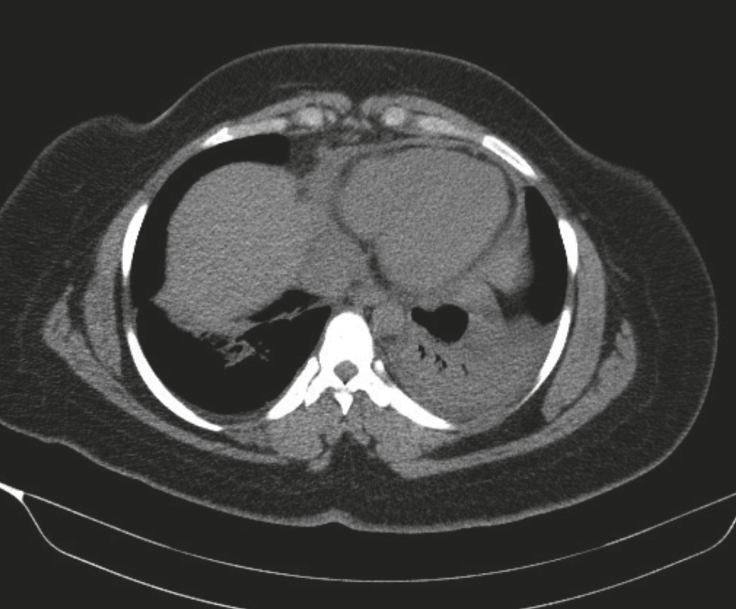

Durante su estancia se documentó infección de vías urinarias por Escherichia coli resistente a ciprofloxacina, para lo cual recibió manejo con piperacilina tazobactam 4.5 gramos intravenosos cada 6 horas durante siete días. Evolucionó con persistencia de febrículas, dolor de tipo pleurítico y elevación de reactantes de fase aguda, se realizó tomografía axial computarizada de tórax ante sospecha de sobreinfección bacteriana que fue descartada, pero con signos de derrame pericárdico en moderada cantidad, sin signos de taponamiento cardíaco (Figura 2). Posteriormente, fue llevada a ecocardiograma transtorácico, con reporte dentro de la normalidad. Se realiza nuevamente troponina de alta sensibilidad con resultado negativo (1.4 VR: 0.0-26.2).

En este caso, la presencia de derrame pericárdico en la tomografía de tórax y la ausencia del mismo en el ecocardiograma transtorácico (ETT) realizado días después, posiblemente sea explicada por su naturaleza autolimitada. Estos hallazgos son consistentes con lo reportado en la literatura, en donde la ausencia de derrame pericárdico u otras anormalidades en el ecocardiogramano excluyen el diagnóstico de pericarditis (13).